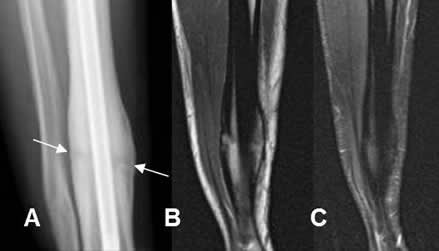

Fig 87. Callo perióstico.

A: Rx AP. Fractura de la tibia estabilizada con clavo de Kuntcher. Clínicamente está consolidada, pero persiste línea radiolúcida entre los extremos.

B: RM coronal en T1 y C: RM coronal en STIR. Callo óseo continuo, sin cambios inflamatorios.